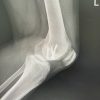

A 77-year-old male with right knee pain was diagnosed with advanced OA. In pursuit of relief, the patient underwent GAE at another hospital. Following the procedure, the patient developed swelling, increased pain, and skin discoloration, necessitating readmission to the same hospital for vascular observation and pain control. Redness, swelling, and pain subsided over a period of 7 days, and the patient was discharged from the hospital (Fig. 1). After a 6-month recovery period, owing to persistent osteoarthritic knee pain, the patient sought further treatment options at our hospital. Upon consultation with our radiologists, an arteriogram was performed 1 year after embolization, and it was ascertained that the genicular arteries remained patent (Fig. 2). Consequently, a decision was made to proceed with total knee arthroplasty to manage OA. During arthroplasty, bone samples of bone cuts from the weight-bearing distal femur and proximal tibia were sent for histopathological examination, and the results were negative for osteonecrosis (Fig. 3). The post-operative period involved meticulous monitoring of complications such as wound dehiscence, tissue necrosis, and infection. Fortunately, aside from the mild erythema observed around the knee a week after the procedure, which did not require any treatment, the wound healed well without any complications, with standard rehabilitation of same-day walking, and ROM exercise could be initiated (Fig. 4 and 5). After 1 year of follow-up, the patient experienced relief of knee pain and achieved a knee range of motion of up to 0°–120° and back to his day-to-day activities, indicating a successful outcome following total knee arthroplasty (Fig. 6 and 7).